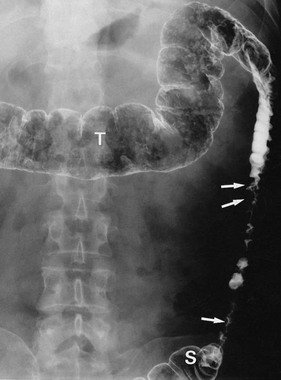

Pericolic abscess represents a further extension of the pathological process just described. The clinical presentation is similar at first but fails to resolve with antibiotics. The patient suffers persistent pain and tenderness, a swinging pyrexia and incomplete obstruction due to spasm of bowel wall muscle. Sometimes a pericolic abscess presents as ‘pyrexia of unknown origin’ or even systemic sepsis (septicaemia). A pericolic abscess may drain spontaneously into bowel, producing an attack of purulent diarrhoea; the condition then resolves. Diagnosis of a pericolic abscess is made on CT scan. A contrast enema may show leakage of contrast into the abscess cavity (see Fig. 29.5).

Fistula formation can occur when an inflamed diverticulum lies close to another hollow viscus. Inflammatory adhesions develop and the diverticulum then ruptures into the other viscus. A fistula between large bowel and small bowel (see Fig. 29.6) causes diarrhoea. A vesico-colic fistula causes pneumaturia and severe urinary tract infection. A fistula into the vagina after a previous hysterectomy causes a purulent vaginal discharge. Diverticular disease is the most common cause of these types of fistula but they may also be caused by Crohn's disease and sometimes colorectal cancers.

Diverticular disease occasionally presents with large bowel obstruction due to acute inflammatory thickening, muscle hypertrophy and spasm. Incomplete obstruction is more common and presents as severe constipation. Chronic diverticular inflammation sometimes causes local fibrous strictures, particularly in the sigmoid, which cause intermittent bouts of constipation when the stool is dry. When detected radiologically or endoscopically, these strictures must be distinguished from malignancy or Crohn's disease by biopsy (Figs. 29.5 and 29.7).